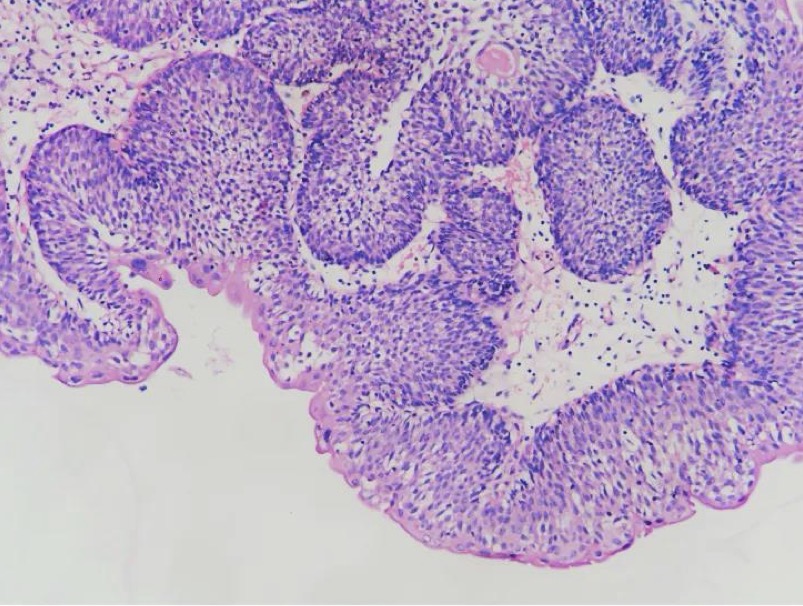

A- identify

B- describe

C- originate from ?

A- Colonic adenoma

B- Tubular colonic adenoma consisting mostly of round or oval glands

C- from benign epithelial tissue